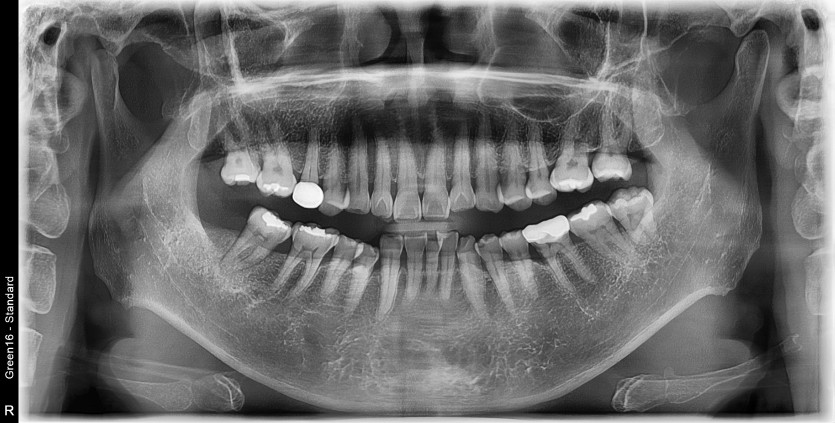

#38 사랑니 발치

구강 외과 전문의가 당일 발치했습니다.